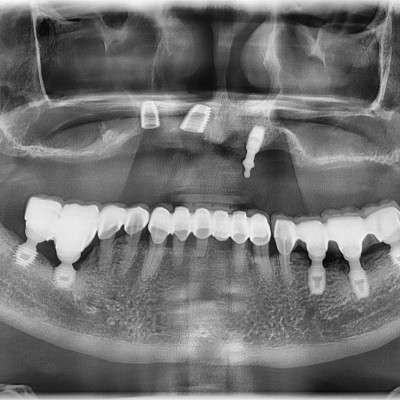

• 8

임플란트 재수술 #11.22 타원 임플란트 제거 후 임플란트 재 수술 + 치조골 이식술 시행하였습니다.

작성자 이턱이 작성일 01-27 조회 110